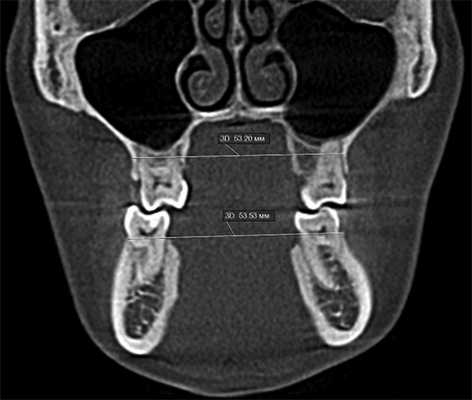

3. Анализ трансверзальных размеров челюстей. Трансверзальный размер челюстей проводят согласно Penn анализу, который впервые был предложен профессором Robert Vannarsdall в Пенсильванском университете для оценки скелетного несоответствия челюстей [2]. Измеряют межмолярное расстояние на нижней челюсти, ориентируясь на вестибулярную кортикальную пластинку на уровне бифуркации нижних моляров, затем трансверзальный размер верхней челюсти измеряется между нижними точками скулоальвеолярного гребня. Верхняя челюсть в норме шире нижней на 5 мм. Если разница составляет 2—5 мм, возможна ортодонтическая коррекция за счет изменения инклинации боковой группы зубов при условии возможности достижения оптимальной окклюзии; до 2 мм — хирургически ассистированное расширение верхней челюсти (рис. 2) [3].

Рис. 2. Измерение трансверзальных размеров челюстей. Ширина верхней челюсти 53,20 мм, нижней — 53,53 мм.